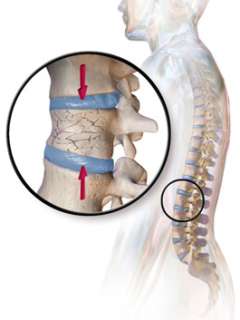

What is Osteoporosis?

Osteoporosis is a weakening of your bones, which increases the risk of a fracture. People with osteoporosis have bones that break too easily (for example, after a fall on the sidewalk).

Does Osteoporosis Cause Bone Pain or Achy Joints?

It is a common misconception that osteoporosis usually causes bone pain. In fact, most people have no symptoms unless there is a fracture. So a person can be completely free of pain and still have osteoporosis. Vertebral fractures (in the spine) can also be painless but cause progressive loss of height over time.

How Does Hyperparathyroidism Cause Osteoporosis?

Answer: Hyperparathyroidism causes one or more of the parathyroid glands to produce too much parathyroid hormone (PTH). PTH increases bone turnover, and too much PTH causes cortical bone thinning especially in the femoral neck (thigh) and distal radius (forearm).